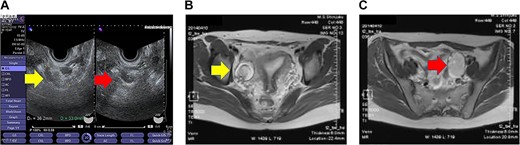

Transvaginal ultrasonography revealed a 3–4-cm diameter mass on each ovary (Fig. 1A) and a normal-sized uterus. Magnetic resonance imaging (MRI) revealed bilateral ovarian cystic tumors with fat tissue (Fig. 1B and C). The laboratory values, including levels of tumor markers (e.g. CA-125, CA 19-9 and alpha-fetoprotein), were within normal limits. The patient was diagnosed with mature cystic teratomas of the bilateral ovaries. Because the ovarian tumors were relatively small during initial examination, a 3-month follow-up visit was recommended. During the follow-up visit, the patient requested surgery for persistent lumbago. Single-port laparoscopic surgery, which is indicated for benign ovarian cysts, was recommended based on surgical indications at our department.

Imaging studies of the pelvis. (A) Transvaginal ultrasound image showing a right ovarian cyst (left arrow) and a left ovarian cyst (right arrow). (B) Axial T2-weighted MRI showing a right ovarian cyst (arrow). (C) Axial T2-weighted MRI showing a left ovarian cyst (arrow).